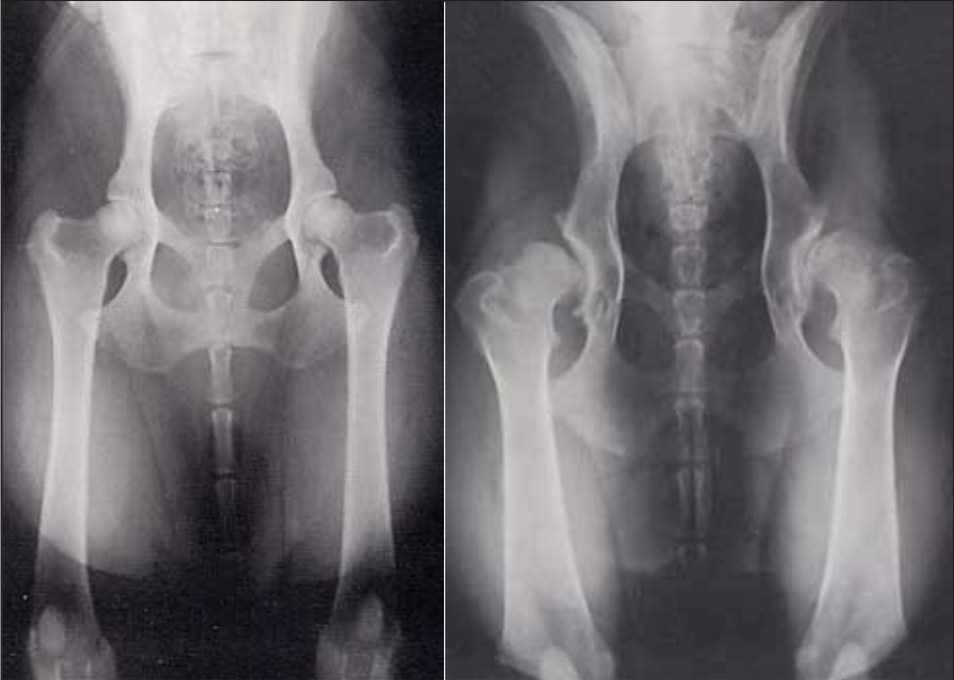

На первой стадии рентгенографическая картина покажет наличие небольших остеофитов и небольшое сужение щели сустава, также будут отмечаться очаги деструкции ткани. После физических нагрузок на тазобедренное сочленение будет появляться боль и дискомфорт, что проходит после снятия нагрузки с сустава.

Для второй степени характерно разрастание костных отростков – остеофитов на головке бедренной кости и в пределах вертлужной ямки, также на снимке становится видно, что щель сустава сужена до четверти от своего анатомического размера. Плюс возможны подвывихи бедра из-за остеофитов.

При 3 степени развития патологии на рентгеновском снимке будут заметны все более явные деструктивные явления в головке бедренной кости и вертлужной впадине, щель сустава, как правило, полностью исчезает. Симптоматика на 3 стадии все более явная:

Диагноз врачом ставится на основании диагностических мероприятий, в данном случае рентгенологическое и ультразвуковое исследования позволяют определить степень заболевания и текущее состояние сустава. Инструментальное и лабораторное исследования также применяются, они необходимы для уточнения и выбора методики лечения патологии.